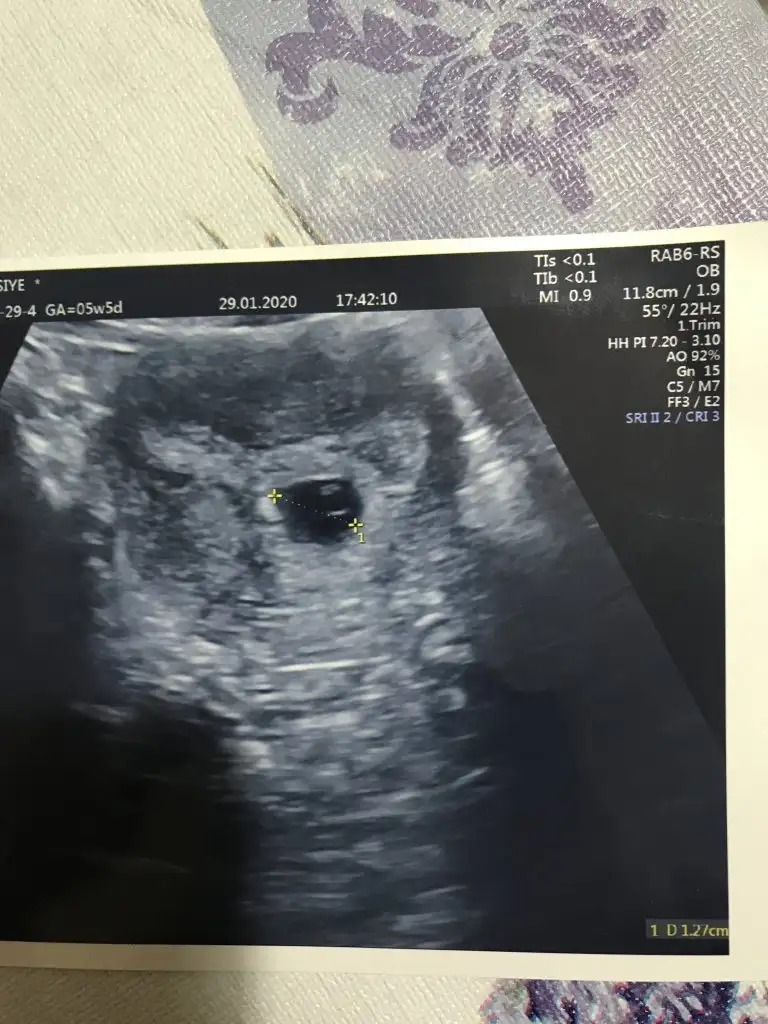

Doktor dan geldim kese ve yolk gözüktü 10 gün sonrada kalp atışı 💓 için çağırdı